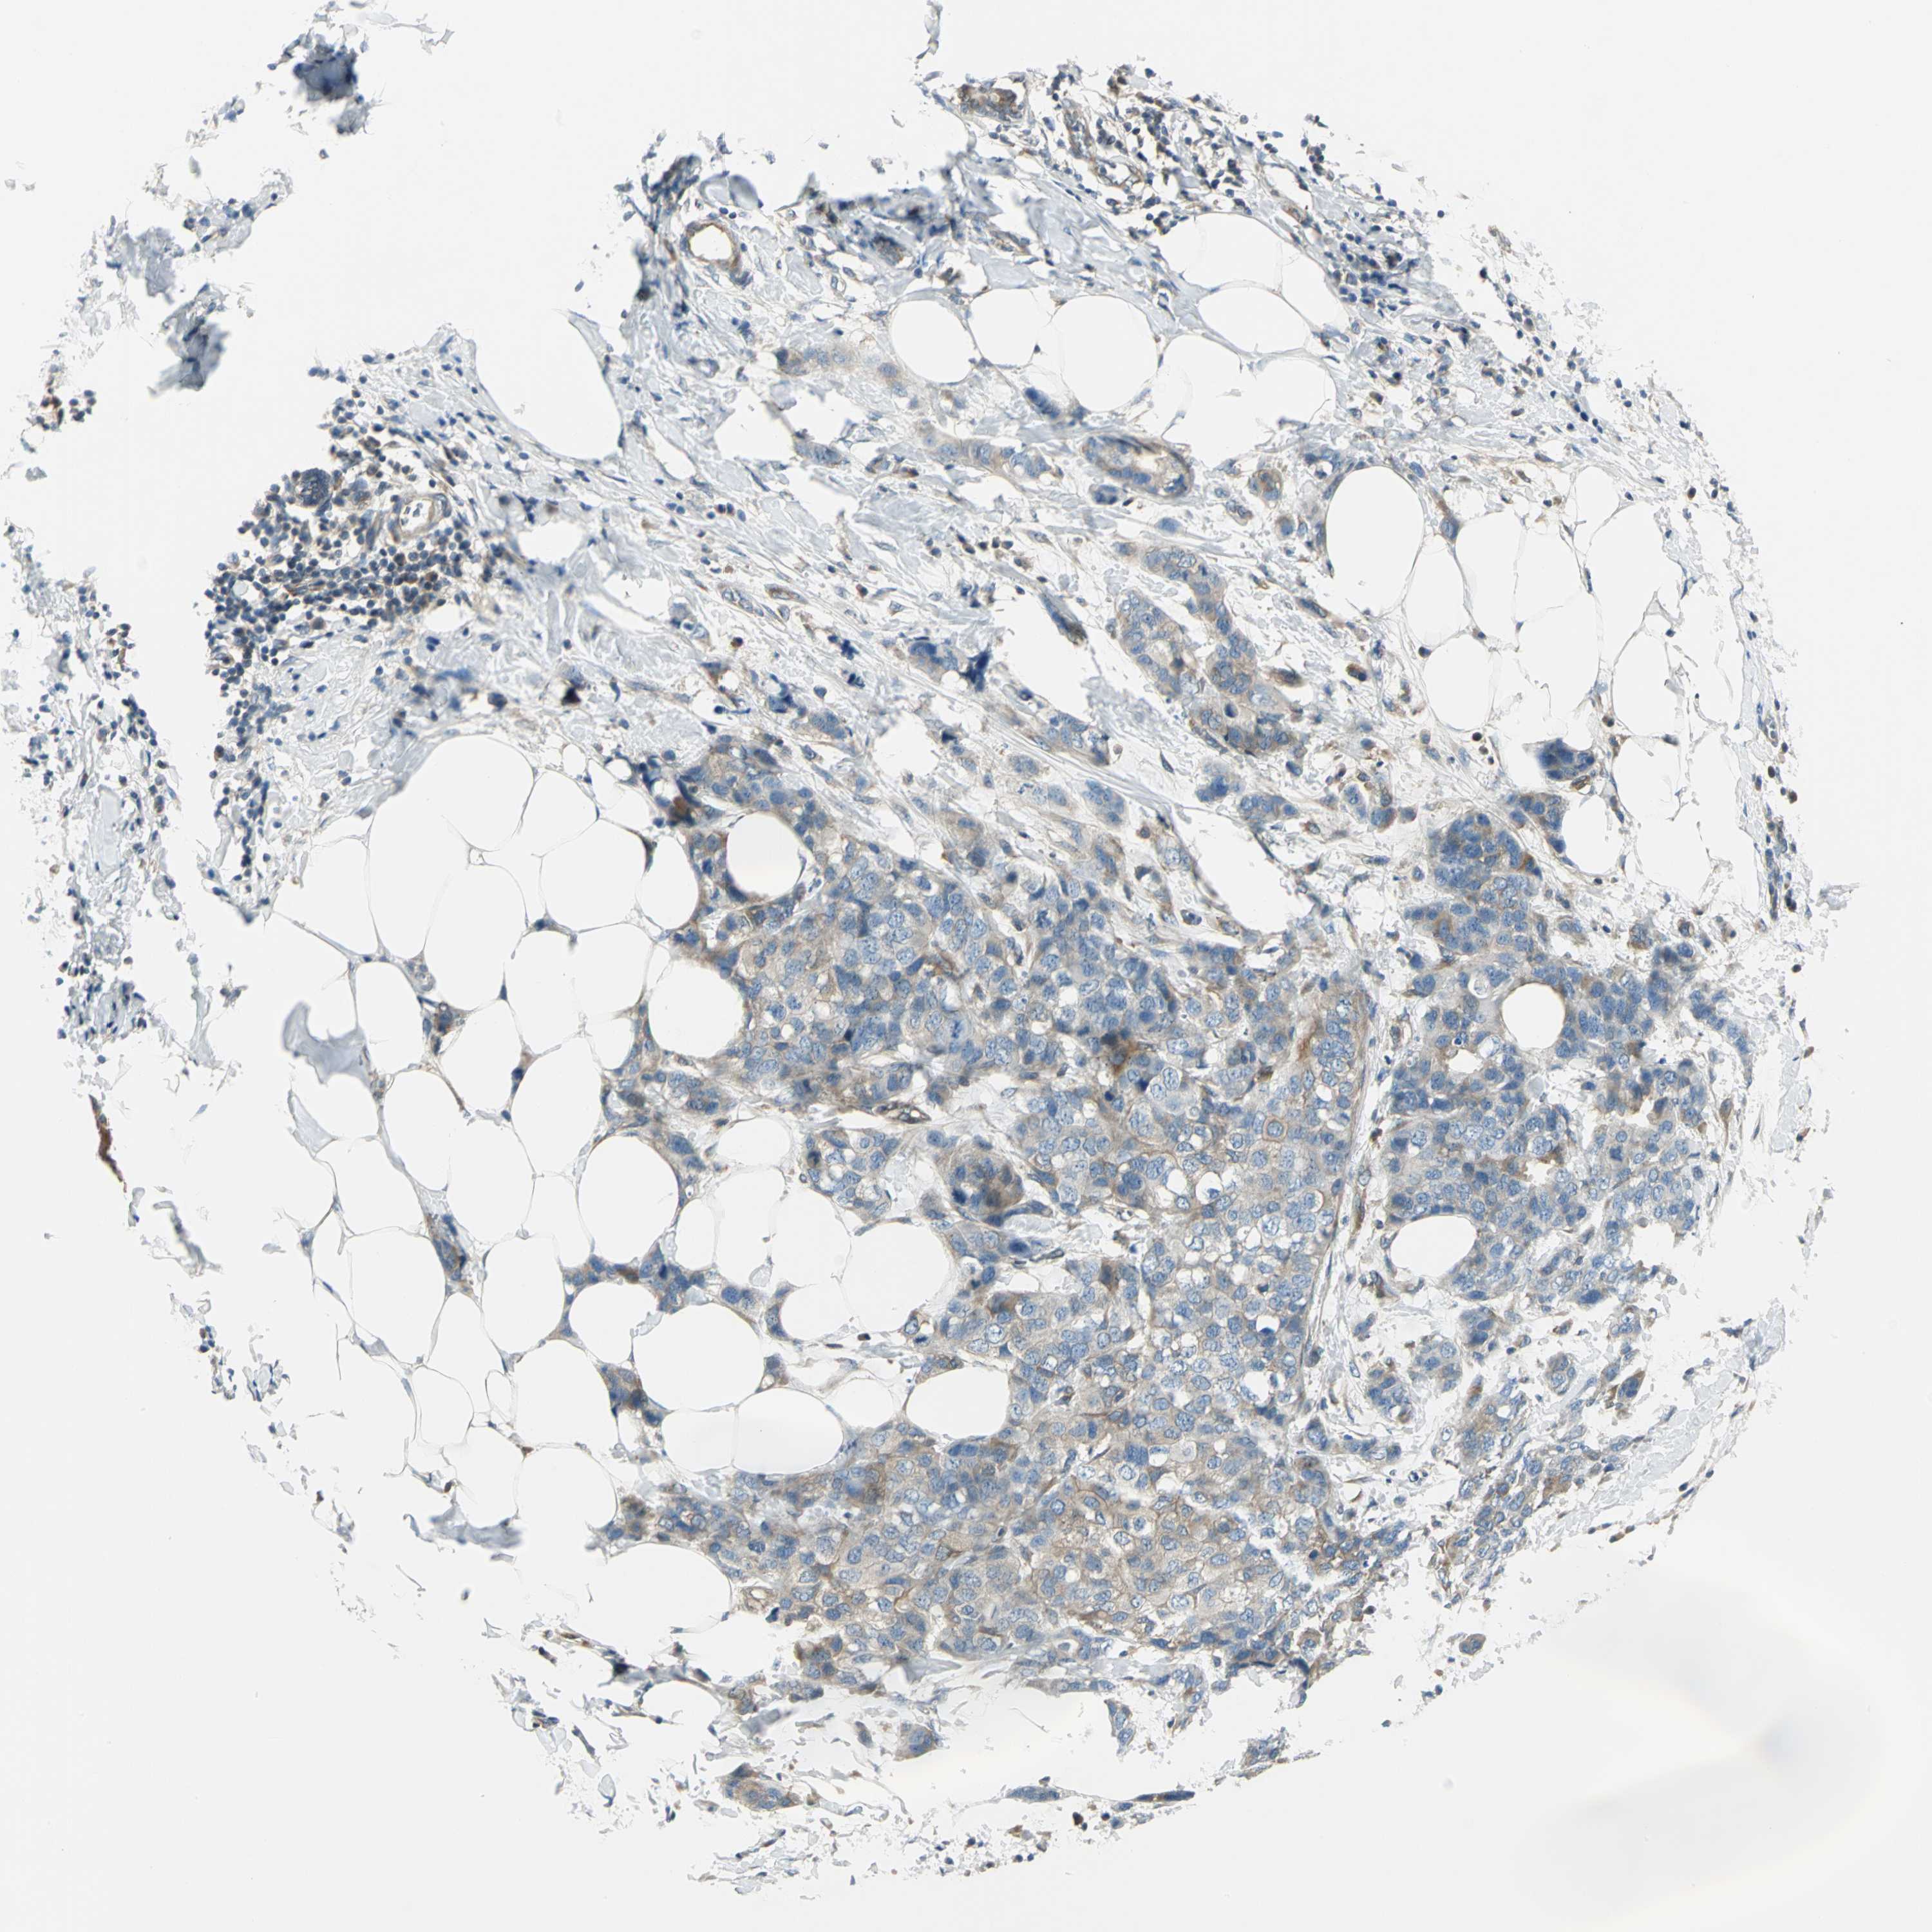

CANCER BREAST CANCER Show tissue menu

BRCA TCGA BRCA VALIDATION PROTEIN EXPRESSION